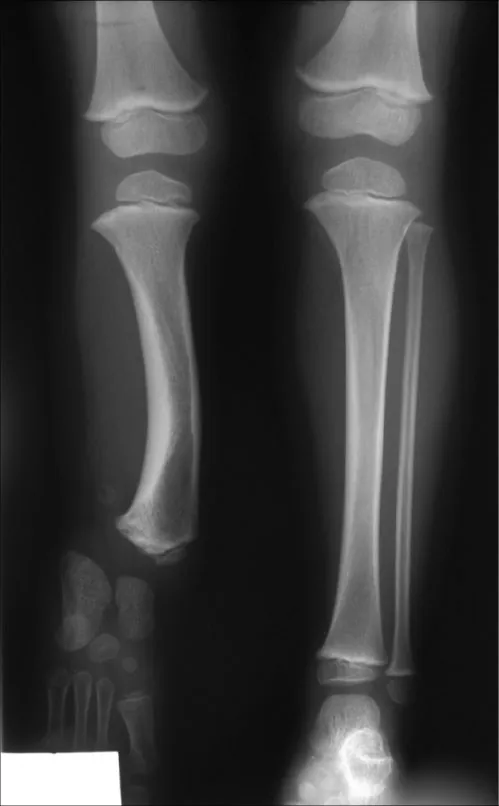

More than 50 percent of people have discrepancies in leg length (OrthoInfo, 1995–2023), but when the difference is less than 1.5 centimeters, it is often not apparent, is often without symptoms, and may not even be measured and confirmed. When the discrepancy between limbs is approximately 1.5 to 2 centimeters (or more), patients are likely to seek care and are evaluated for treatment (Figure 25.12).

The image is an X-ray showing the lower legs and feet of a child, presenting a clear view of the tibia, fibula, knee, and ankle joints, as well as the bones of the feet.

Figure 25.12 Discrepancy in leg length: this patient’s left leg is shorter than the right, with a missing fibula and notable bowing of the tibia. (credit: "Radiographic presentation of a 6 years old patient with fibular hemimelia type II" by National Library of Medicine, CC BY 2.0)